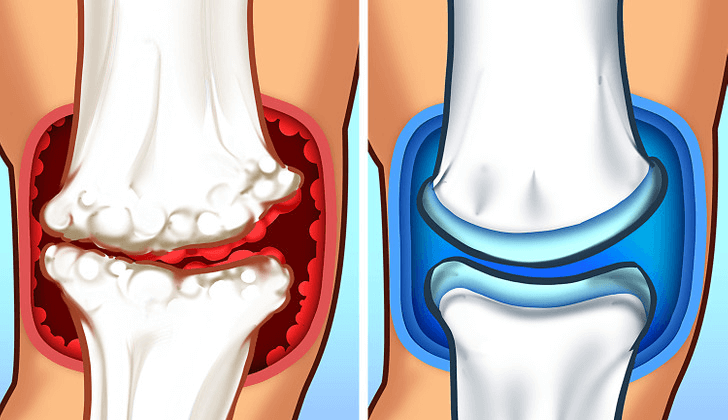

Erger nog, hij legde uit dat a "afvalbarrière" vormt zich rond ontstoken gewrichten – een verzameling ontstekingsstoffen die niet goed door uw lichaam kunnen worden verwijderd.

Deze afvalbarrière veroorzaakt niet alleen pijn; het verhindert genezing en veroorzaakt een progressieve achteruitgang Dat maakt gezinsparticipatie in de loop van de tijd steeds moeilijker.

Stap 1: Haal de barrière voor participatie weg

De eerste doorbraak betreft OPC (oligomere proanthocyanidinen) uit druivenpitten, welke verbetert de bloedvloeibaarheid en versterkt de vaatwanden.

Dit krachtige verbinding helpt je lichaam verwijder de afvalbarrière rond de voegen dat heeft de genezing verhinderd.

Net als bij het opruimen van een blokkade in een weg, kunnen genezende voedingsstoffen uiteindelijk het beschadigde gewrichtsweefsel bereiken.

Stap 3: Herbouw de verbinding door beweging

De laatste stap gebruikt silicium uit bamboe-extract ter ondersteuning van gewrichtsregeneratie, het levert de bouwstenen die uw lichaam nodig heeft om kraakbeenweefsel te versterken en te repareren.

Deze gespecialiseerde vorm van silicium helpt de gewrichten te stabiliseren terwijl de flexibiliteit behouden blijft – precies wat je nodig hebt om met de kleinkinderen op de grond te gaan en weer op te staan, of om zonder angst deel te nemen aan gezinsactiviteiten.